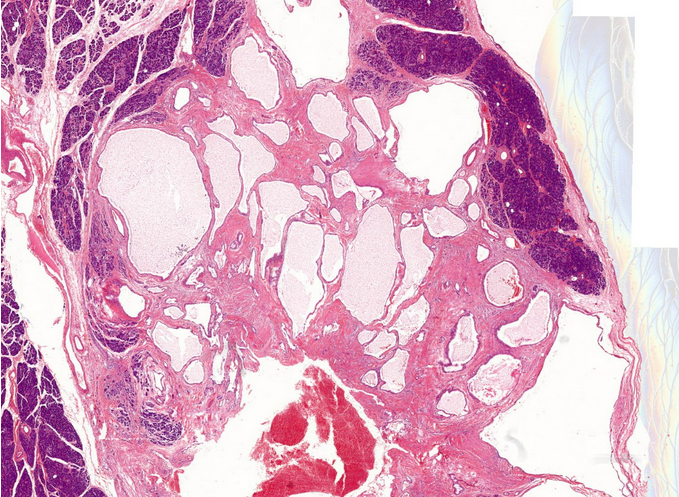

25M rectosigmoid polyp

Dx

Key features

A

Juvenile polyp

Key features:

Characterized by an abundance of edematous lamina propria with inflammatory cells and cystically dilated glands lined by cuboidal to columnar epithelium with reactive changes (gastric type epithelium??)

Dilated glands filled with mucus and inspissated inflammatory debris